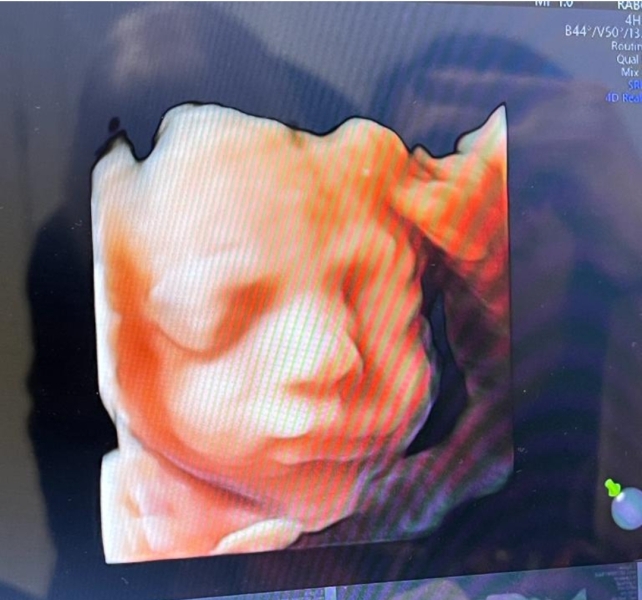

We took our mums to a 3D scan today, it was so lovely 🥰 I already think baby girl has her dad's face shape